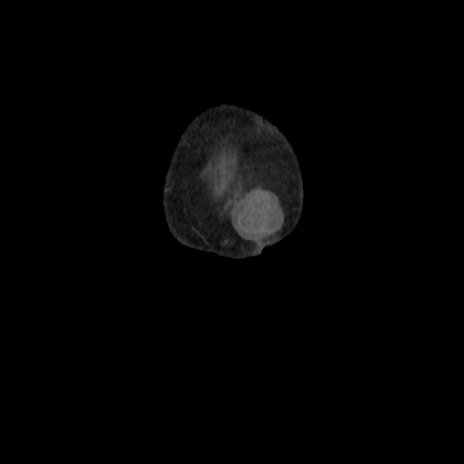

横断像

【症例】80歳代 女性

【主訴】腹部膨満感

【現病歴】他院にて肝硬変にてフォロー中。1週間前から便秘、腹部膨満感、臍部腫瘤あり受診となる。

【既往歴】肝硬変

【身体所見】腹部膨隆あり、皮膚変化なし、疼痛なし。

【データ】WBC 4600、CRP 0.25